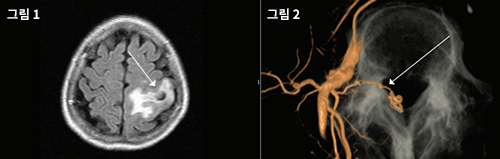

때로는 뇌종양처럼 발작을 일으키기도 하고, 노인성 질환처럼 기억 상실을 동반하는 치매를 일으킬 수 있으며, 뇌경색이나 뇌출혈을 일으켜 뇌졸중으로 진단되기도 하지만 오랜기간 아무런 증상이 나타나지 않을 수도 있다.[그림 1]

또한 작고 복잡한 혈관을 따라 들어가서 색전술을 하거나 수술로도 치료가 가능하다.[그림 2]

그림 1. 마비와 발작을 일으킨 환자의 뇌자기공명영상. 부종과 출혈(화살표)도 있다. 뇌종양이나 경색도 감별하게 되는 소견이다. 경막동정맥루를 의심하고 혈관조영을 시행해서 확진을 확인했다. 의심하지 않으면 진단하지 못하거나 다른 진단을 할 수도 있다.

그림 2. 척추경막동정맥루(Spinal arteriovenous fistula) 혈관조영상. 3차원 혈관조영을 얻어서 여러 각도로 돌려 보면 경막을 뚫고 들어가는 부위에서 동정맥루 혹은 션트(화살표)가 있다. 이러한 영상을 학회에서 발표를 하면 어떻게 이런 영상을 얻었냐고 감탄을 한다. 고가의 장비와 인력과 더불어 적지 않은 시간과 노력이 들어가지만 정작 이러한 결과물에 대한 진단 수가는 하나도 없다. 만에 하나 치료가 않되거나 잘못되면 환자나 보호자들로부터 엄청난 원망을 듣기 때문에 진단과 시술을 할 수록 힘들어지는 구도이다. 이런 여건에서 앞으로 누가 이 일을 맡아서 하게 될지 필자는 염려가 된다.